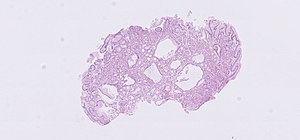

Fundic gland polyp. H&E stain. | |

| LM | polypoid shape (epithelium on three sides), dilated gastric glands (flatted epithelial lining consisting of normal foveolar epithelium), lack of foveolar hyperplasia |

- Polypoid shape (may not be appreciated on microscopy).

- Dilated gastric glands.

- Flatted epithelial lining (consisting of normal foveolar epithelium) - key feature.

- The presence of dysplastic changes should prompt consideration of FAP.